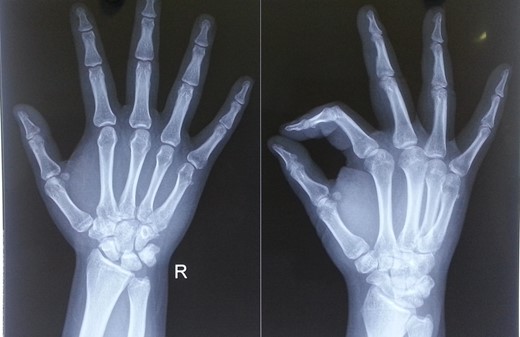

A 28-year-old gentleman presented to us with complaints of pain and swelling of the right hand for 2 hr. He sustained an injury to his hand when his motorbike skid and he landed on the ulnar aspect of his hand and little finger. On examination, there was swelling, tenderness and deformity on the ulnar aspect of his hand. There was restriction of movement of the fifth finger. His wrist movements were normal, and there were no open wounds in hand. Radiological evaluation revealed dorsal dislocation of fifth CMC joint and volar dislocation of distal MCP joint (Fig. 1). Based on clinico-radiological examination, diagnosis of close, fifth floating finger was made. Closed reduction of the dislocations was done under sedation in emergency room, and wrist splint supporting the head of MCs was applied. Immediate post-reduction stability of the joints was assessed and the joints were found to be stable. Post-reduction radiographs (antero-posterior and oblique views) confirmed the reduction of both CMC and MCP joints (Fig. 2). The splint was removed after 3 weeks, and finger and wrist range of motion (ROM) exercises were started. At 6 months follow-up, his finger and wrist ROM were full. Grip strength was comparable on both sides and his movements were pain free (Fig. 3). No abnormalities were detected on the radiographs at 6 months follow-up (Fig. 4).